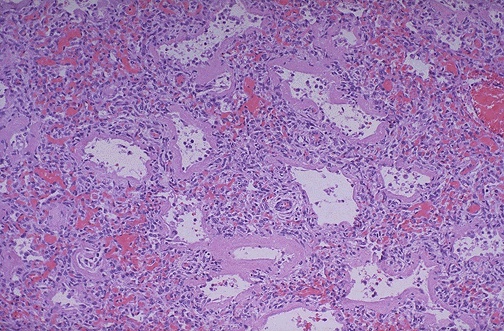

Image 1.2

The lung is shown here at low power microscopically.